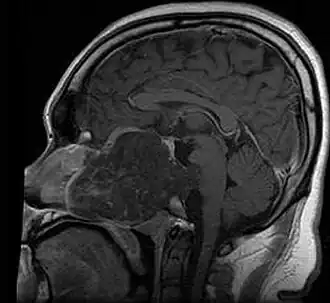

| MRI of extensive clival chordoma in 17-year-old male patient, axial view. Tumor in the nasopharynx extending from nasal cavity to brainstem posteriorly is clearly visible. | |

Chordoma is a rare slow-growing neoplasm (cancer) that arises from cellular remnants of the notochord in the bones of the skull base and spine. The evidence for the notochordal origin of chordoma is the location of the tumors (along the neuraxis), the similar immunohistochemical staining patterns, expression of brachyury, and the demonstration that notochordal cells are preferentially left behind in the clivus and sacrococcygeal regions when the remainder of the notochord regresses during fetal life.

In layman's terms, chordoma is a type of bone cancer, and is classified as a sarcoma.[1] Chordomas are sometimes mistakenly referred to as a brain, brainstem or spinal cord tumors due to their location near those critical structures, but they are not derived from nervous tissue.

In most cases, complete surgical resection followed by radiation therapy offers the best chance of long-term control.[17] Incomplete resection of the primary tumor makes controlling the disease more difficult and increases the odds of recurrence. The decision whether complete or incomplete surgery should be performed primarily depends on the anatomical location of the tumor and its proximity to vital parts of the central nervous system.[18]

Chordomas are relatively radioresistant, requiring high doses of radiation to be controlled. The proximity of chordomas to vital neurological structures such as the brain stem and nerves limits the dose of radiation that can safely be delivered. Therefore, highly focused radiation such as proton therapy and carbon ion therapy are more effective than conventional x-ray radiation.[19]